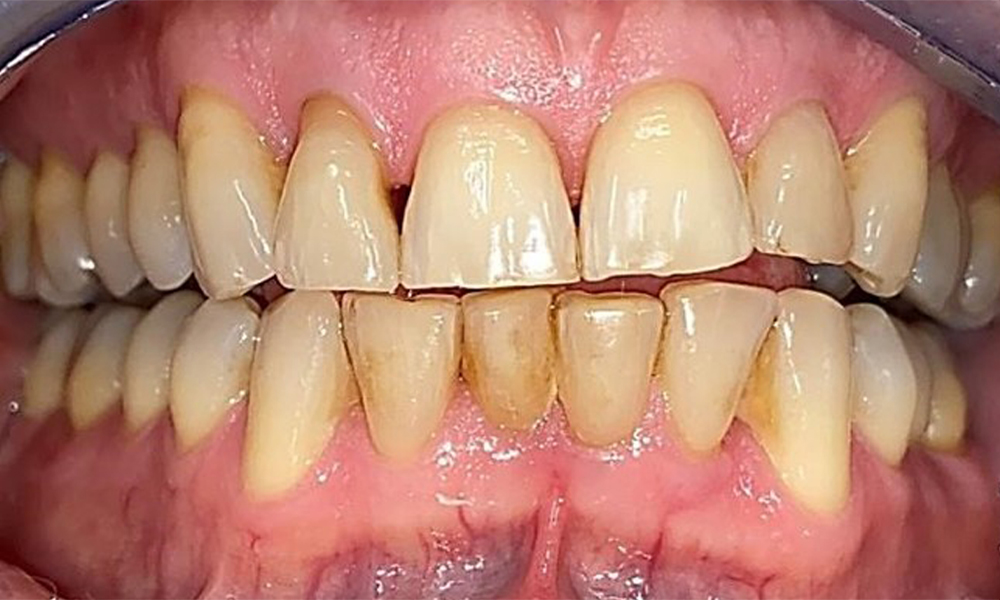

The patient has a full dentition with 28 teeth, which includes amalgam and composite fillings in the molar and premolar regions. There is a visible clinical marginal gap present on tooth 14. Tooth 27 has an adequate gold inlay. There are also generalized attritions and abrasions. (Fig. 2, Fig. 3, Fig. 4, Fig. 5, Fig. 6)

Periodontal findings

The patient has stage II, grade B periodontitis (5). At 1 to 3 mm, the clinical probing depths were within the physiological range. Localized probing depths of 5 mm were observed on the mesiopalatal aspects on both 17 and 27. There are generalized recessions of 1–3 mm with partial loss of the interdental papillae (Fig. 2, Fig. 3, Fig. 4)